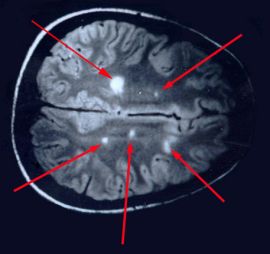

I'm sorry for your sisters troubles. Praying for her. They found white lesions in my brain when I went to the emergency room for vertigo. They were so busy trying to diagnose me with MS, they forgot to mention they found a brain tumor as well. Saw three neurologists, one that pitched a fit because I didn't take the jab. I was told, "We prefer our MS patients be vaxxed." I told them I wasn't even diagnosed and I wasn't theIr patient YET! This was at a huge teaching hospital. I never went back. My GP referred me to another Dr. for the brain tumor. He said there was nothing they could do about it because of it's location. Go home and live your life. Third neuro was for a back problem and while discussing my history, the white lesions came up. He said: EVERYONE has those. They do more harm than good anymore, I swear.